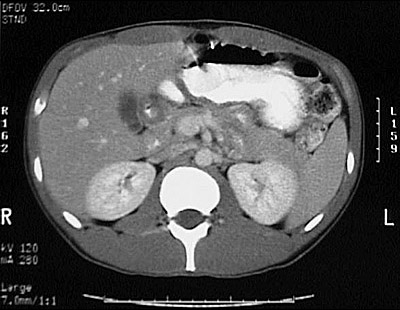

[L2] This is a normal abdominal CT scan with contrast demonstrating the liver and gallbladder and spleen and stomach filled with contrast and colon and pancreas and right kidney and left kidney and aorta and vertebral body and rectus abdominis muscle in the upper abdomen.